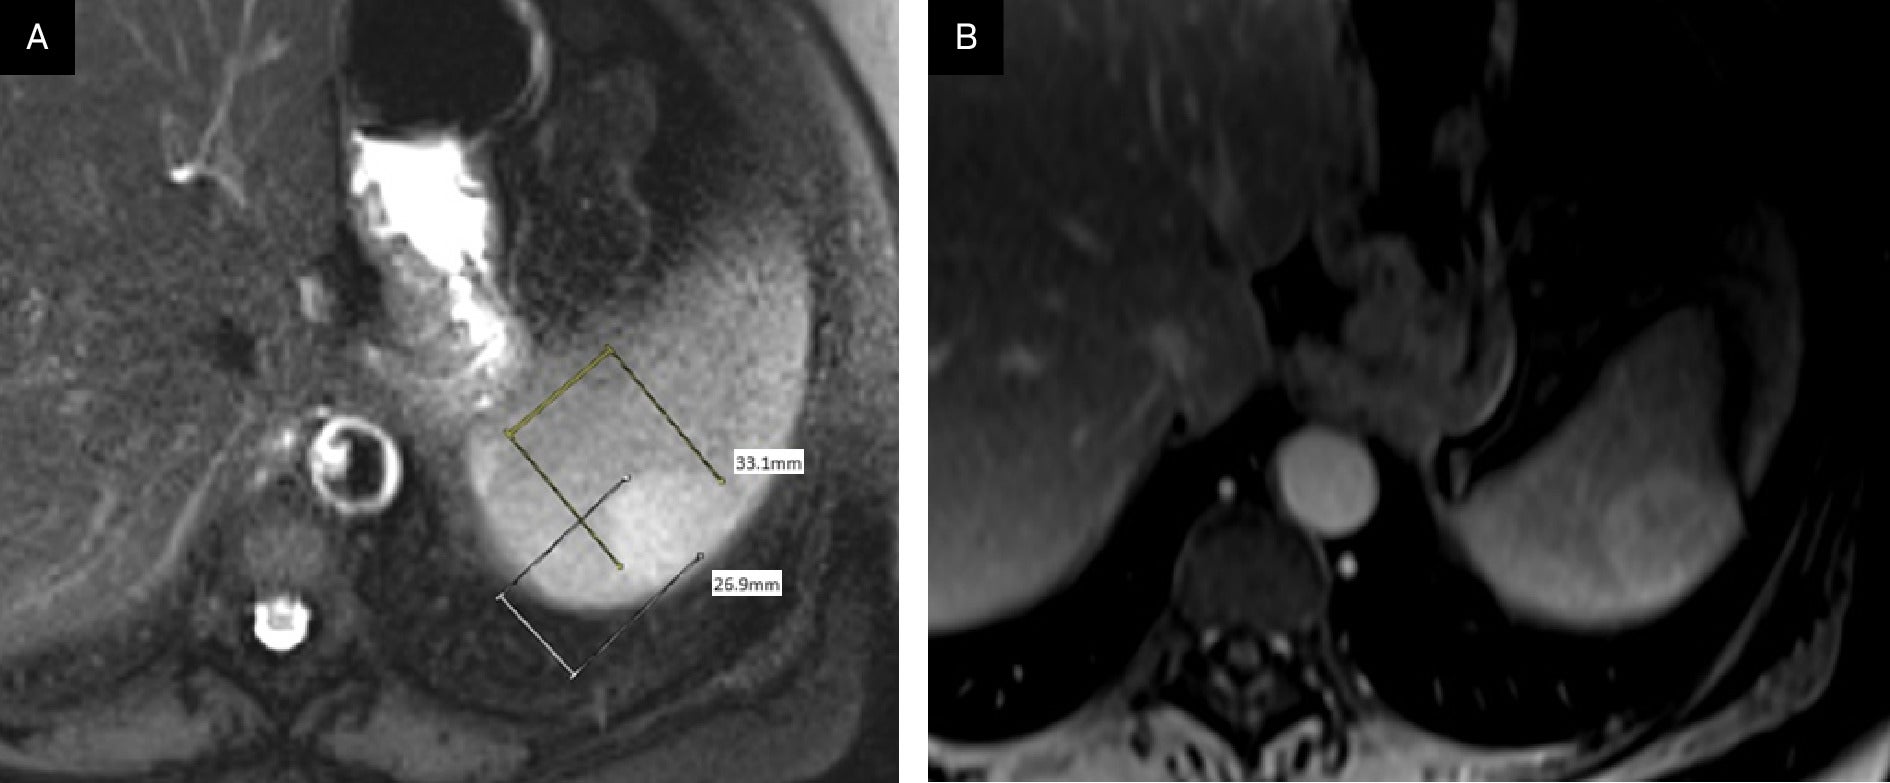

Given the patient’s cancer history and anemia, CT imaging was performed, demonstrating a mildly hyperdense 13.1 cm lesion in the portal venous phase ( Figure 1 ), with no other significant findings. Multiphasic, multiplanar MRI demonstrated a 3.3 cm × 2.7 cm mildly T2 hyperintense, enhancing lesion in the posterior aspect of the spleen ( Figure 2 ).

(A) T2 axial MRI demonstrates a mildly hyperintense 3.3 cm × 2.7 cm solitary lesion in the periphery of the spleen. (B) Post-contrast MRI scan in the portal venous phase demonstrates mildly heterogeneous enhancement.